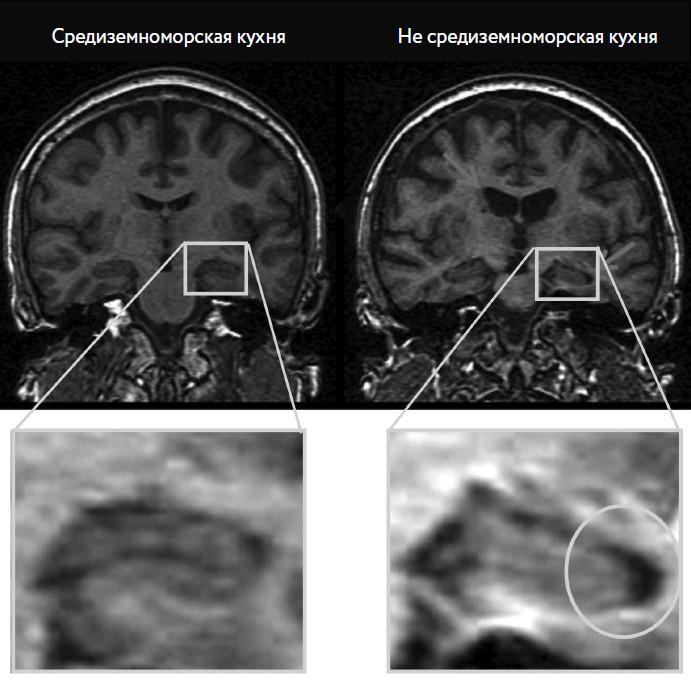

Таким образом, мы добрались до основного посыла этой главы: крупные метаанализы (анализы, которые объединяют данные нескольких исследований) показали, что средиземноморская диета снижает риск возникновения депрессии до 30 %. Также ученые обнаружили, что определенные области мозга людей, придерживающихся средиземноморской диеты, с возрастом теряют в объеме меньше, чем у людей, предпочитающих другое питание. И о какой области мозга идет речь в первую очередь? Правильно, о гиппокампе. Чтобы стало понятнее: у тех, кто придерживается средиземноморской диеты, гиппокамп больше, а душевное состояние лучше (рис. 1.3).

Рис. 1.3. В одном из исследований ученые из Нью-Йорка сравнили группы из более чем 50 участников: одни больше придерживались средиземноморской диеты, а другие меньше.

На представленных вверху снимках виден поперечный разрез мозга двух участников. Человеку, чей мозг представлен слева, на момент снимка было 52 года, и он придерживался исключительно средиземноморской диеты. Мозг выглядит нормальным и здоровым.